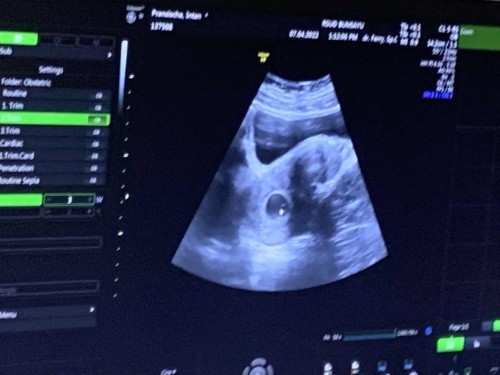

#pleasehelp #ingintahu #firstbaby Maaf ya izin bertanya, usia kehamilan dari aplikasi baru 6minggu 1hari, tapi usia usg udah 8 minggu 1 hari, saya selama ini selalu mens rutin dan tepat waktu, apakah memungkinkan ukuran hitungan usg dan hitungan manual berbeda?#firstmom

Ibu hamil